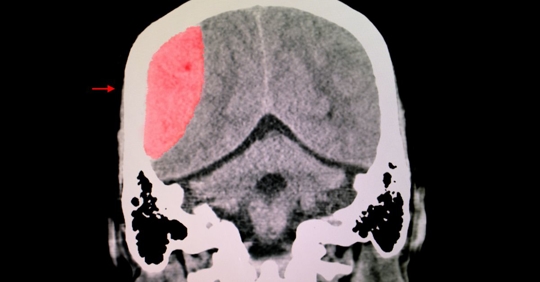

Traumatic Brain Injuries (TBI):

Causes: TBIs often result from severe blows to the head, whether due to car accidents, falls, sports injuries, or violent assaults. They can occur when the brain hits the skull or when an object penetrates the brain tissue.

Impact: TBIs can lead to a range of symptoms, from concussions to severe cognitive impairment, memory loss, personality changes, and in some cases, permanent disability.